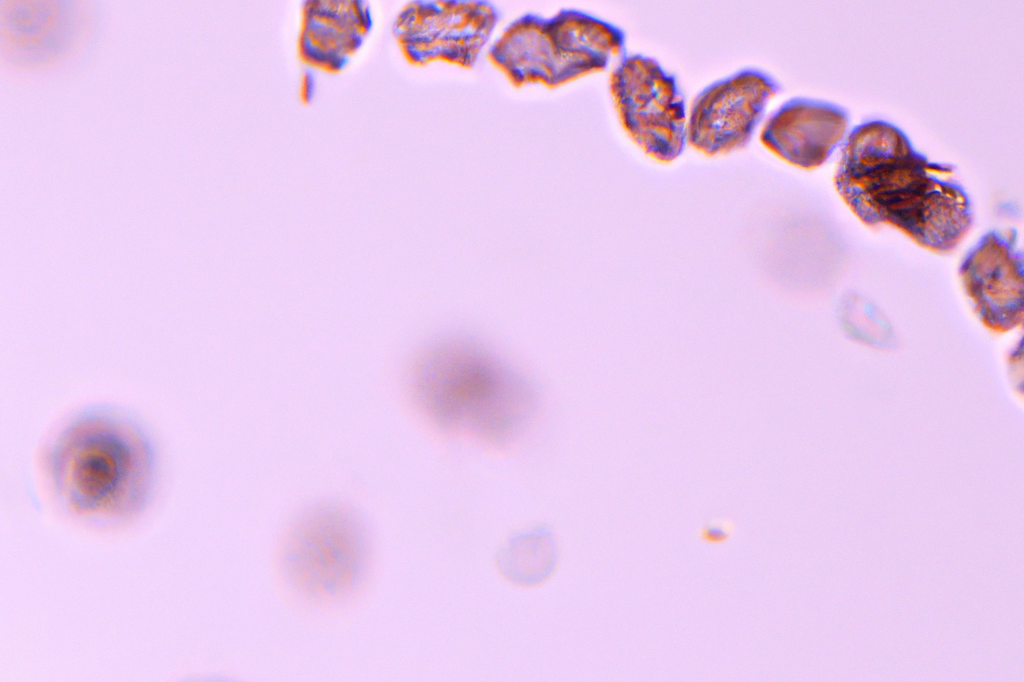

Bioregenerative Therapie

Hier erfolgt die Heilung durch Aktivierung körpereigener Regenerationsprozesse und Reparaturmechanismen. Wir wenden moderne Therapien wie PRP und Hyaluron Injektionen an.